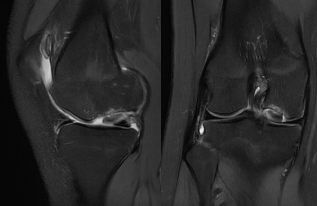

陈某在一个多月前开始感到右膝关节疼痛,活动也受到影响。虽然服用止痛药后有所好转,但病情反复发作且逐渐加重。在当地医院进行磁共振(MRI)检查后,真相浮出水面:她的右膝关节发生了剥脱性骨软骨损伤。

关节镜下视野——屏幕显示右膝关节内侧髁负重区出现大面积软骨剥脱(范围约3.0cm x 2.0cm),软骨下骨裸露,如同墙皮脱落露出了水泥墙基,这是导致疼痛的直接原因。